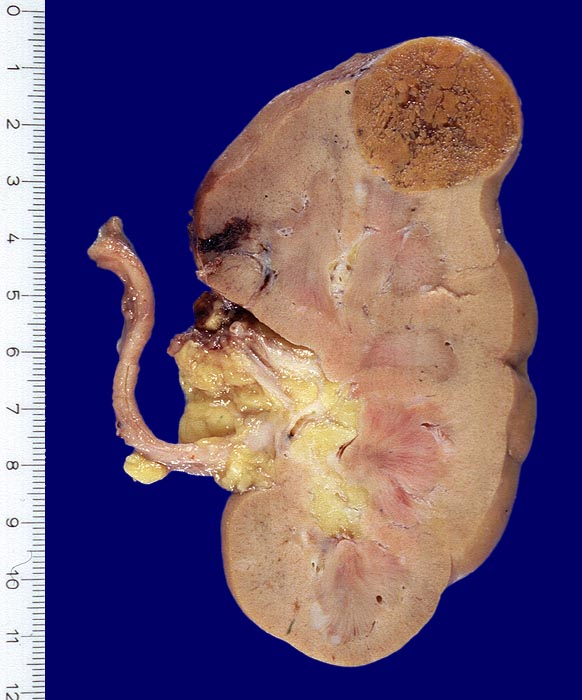

Onkozytom der Niere

Exzentrisch in der Nierenrinde des Oberpols lokalisierter caramelfarbener scharf begrenzter Tumor mit Einschlüssen von zackig begrenzten grauen Arealen. Die weissen Herde im Bereich der Mark-Rinden Grenze entsprechen reaktiven Entzündungsinfiltraten.

Histologie: aus onkozytären Zellen aufgebauter Tumor. Die weissen Areale entsprechen grossen Lymphfollikeln. Immunhistochemisch keine Anhaltspunkte für Malignität des Infiltrates.